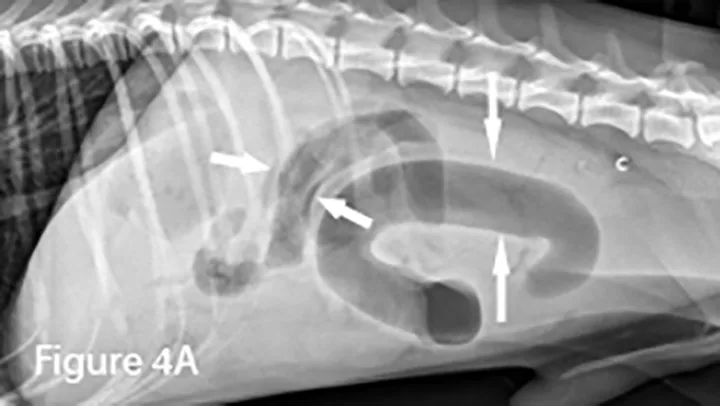

4. Intussusception Causing Small Bowel Obstruction

Marked diffuse small intestinal dilation (arrows). (C = colon)

Invagination of 1 portion of the GI tract (intussusceptum) into the lumen of another (intussuscipiens); this is often referred to as the target sign when seen in the transverse plane because of the multiple layers of adjacent intestinal walls.